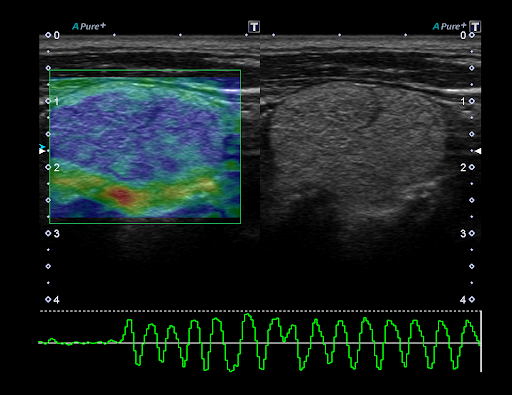

Real-time Elastography*

Эластография в реальном времени обеспечивает цветовое картирование, отражающее деформацию тканей и их эластичность после компрессии. Данная технология необходима для четкой локализации и оценки пальпируемых массы с исключительной точностью, чувствительностью и воспроизводимостью.